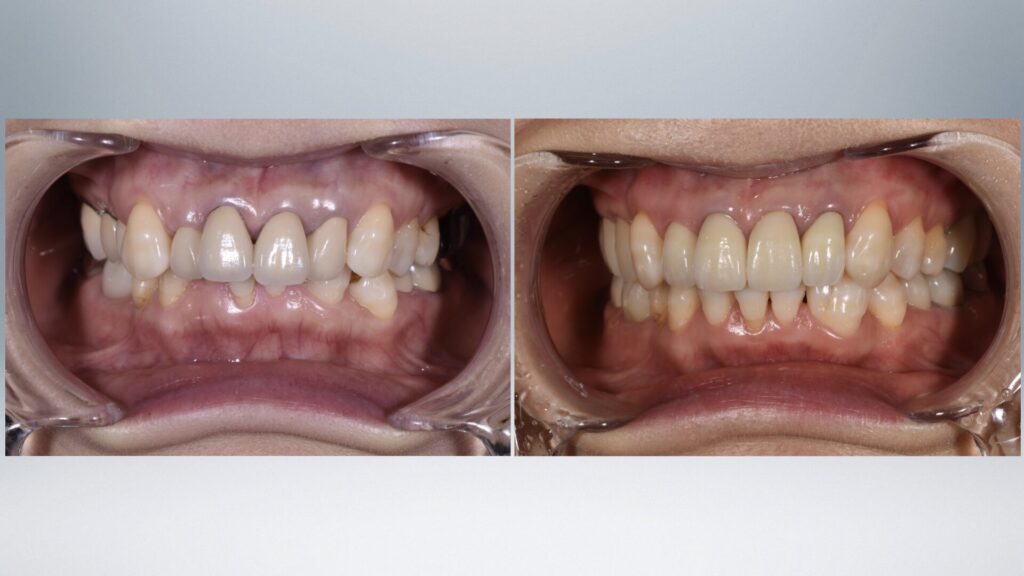

Before

After

| 治療方法 | 初診時に歯列不正を伴う多数の失活歯(神経がない歯)があり、将来的な歯牙破折による治療の複雑化が予測されました。各歯牙に問題が起こる前にマウスピース矯正により歯牙のポジションを整え、セラミック修復を行い将来的なリスクを軽減することに努めました。 |